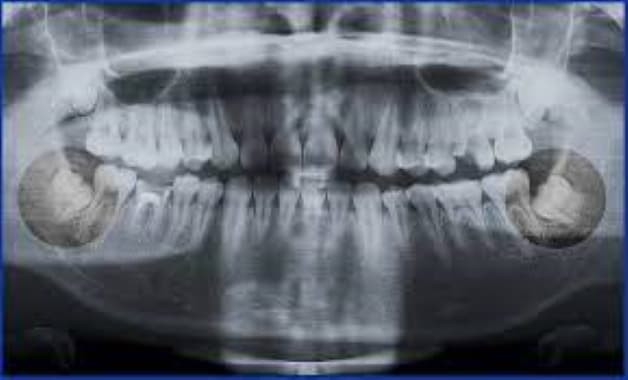

Răng khôn nằm ở vị trí trong cùng và là răng mọc sau cùng trên cung hàm

Răng khôn là răng mọc cuối cùng. Loại răng này thường xuất hiện ở tuổi thiếu niên hoặc đầu tuổi hai mươi. Răng khôn giữ vai trò quan trọng trong sự gắn kết của nướu răng. Tuy nhiên, răng khôn mọc lệch có thể gây tổn thương cho các răng bên cạnh, cho dây thần kinh hay xương hàm, trong trường hợp đe dọa sức khỏe thì cần phải nhổ bỏ. Hầu hết người lớn có 4 răng khôn tuy nhiên cũng có người có ít hoặc nhiều hơn, được gọi là răng dư (răng thừa).